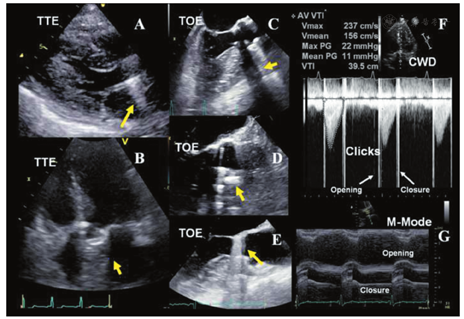

笼-球型机械性瓣膜形同鸟笼状,显示球瓣在心室侧运动。2D超声显示金属支架为强回声,而球瓣近端表面回声稍弱。动态观察,阀体在笼内前后移动。二尖瓣位置的笼-球瓣,收缩期阀体定位在缝合环内。M超声显示笼、缝合环和球瓣分别呈现4种不同的回声。单叶侧倾碟瓣表现为单一回声在心室面呈前后运动。这种瓣叶相对于瓣环的开放角度在60°~80°,导致出现大小不同的两个瓣孔。M型超声显示瓣叶开放形成多向反射的强回声。双叶PHV显示为两片独立的碟瓣,二者几乎同步开放和关闭。瓣叶相对于瓣环的开放角度在75°~90°,开放的瓣膜包括三个瓣孔:一个较小的两瓣叶间的狭缝样的中央孔和两个较大的呈半圆形的侧孔(图2)。

血流通过功能正常的PHV的血流特征不同于自体瓣膜。前向血流的特征因瓣膜位置、瓣孔的形状和数量不同而各异[7,14,83,84,85,97,98,99]。双重轮廓的多普勒频谱常见于机械性PHV中。PHV血流的多普勒频谱还包括由于阀体开启和关闭所产生的短暂、强回声、快速度的喀喇音信号(图4F,图5E)。在所有切面均应显示瓣孔被彩色血流完全充填(图2B)。

在单叶碟瓣,通常射流通过大的主孔(横截面呈半圆形射流)时产生浓密的较低速度血流,而射流通过小孔时呈暗淡的较高速度血流(依据立柱数量不同可为2~3束)。同样地,射流通过双叶机械性瓣膜的两个侧孔时产生浓密的低速血流,而通过中央孔产生暗淡的高速血流(图2F)。三股独立的射流构成前向跨瓣血流的特征性模式(图2B)。笼-球型PHV显示为血流沿整个球瓣周边通过,形成两个曲线状侧流并在中央部位形成涡流区。人工生物瓣膜前向血流模式为单一的中央性血流。